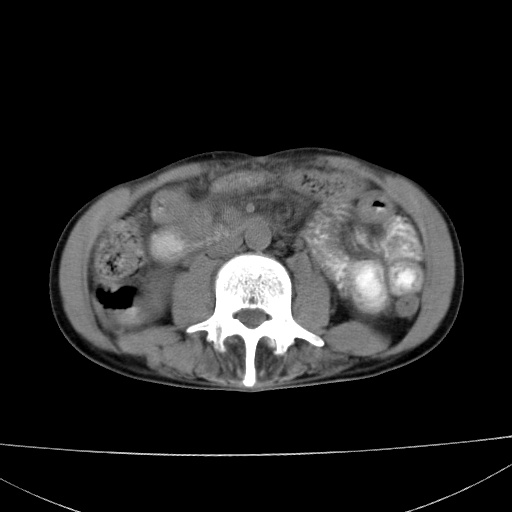

患者 男  41岁,右上腹痛伴腹泻10天,8年前有乙肝,本次b超查肝右叶占位来做ct ,请会诊!

肝硬化\\脾大\\门静脉高压,胃底静脉曲张可能性大.肝右叶肝癌肝内转移,建议增强.左侧小结石.

肝右叶肝癌肝内转移,建议增强

支持肝癌伴肝内转移,脾大,门静脉高压,胃底静脉曲张。

1)考虑肝癌;建议行ct增强扫描检查。2)脾大,门静脉高压,胃底静脉曲张。3)左肾小结石。

1)考虑肝癌及门脉瘤栓,建议行ct增强扫描检查。2)脾大,门静脉高压,胃底静脉曲张。3)左肾小结石。

结合病史;考虑肝癌。门静脉高压,脾大。胃底静脉曲张。

1)考虑肝癌;2)脾大,门静脉高压,胃底静脉曲张。3)左肾小结石。建议行ct增强扫描检查。